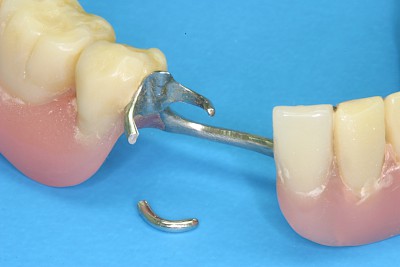

Hält eine Teilprothese kann es auch sein, dass das Verbindungselement defekt oder verlorengegangen ist. In diesen Fällen ist zu prüfen, ob eine Klammer abgebrochen oder ein Verbindungselement wie z. B. eine Krone fehlt. Ist dies der Fall muss ein Zahnarzt gerufen werden.

Bei manchen Prothesen verschlechtert sich der Halt, weil die Haltewirkung der Verbindung zwischen der Prothese und den Restzähnen oder Implantaten nachlässt. Nicht selten sind auch einzelne Verbindungs- bzw. Verankerungselemente einfach "verloren" gegangen (verschluckt, ausgespuckt und ganz selten aspiriert!). Manchmal stecken die Kronen, die die Prothese mit den Restzähnen verbinden, in der herausnehmbaren Prothese. In Ausnahmefällen sind die Ankerzähne oder Implantate selbst nicht mehr im Knochen fest verankert und gehen mit der Prothese insgesamt raus. In allen diesen Fällen sollte der Zahnarzt gerufen werden.